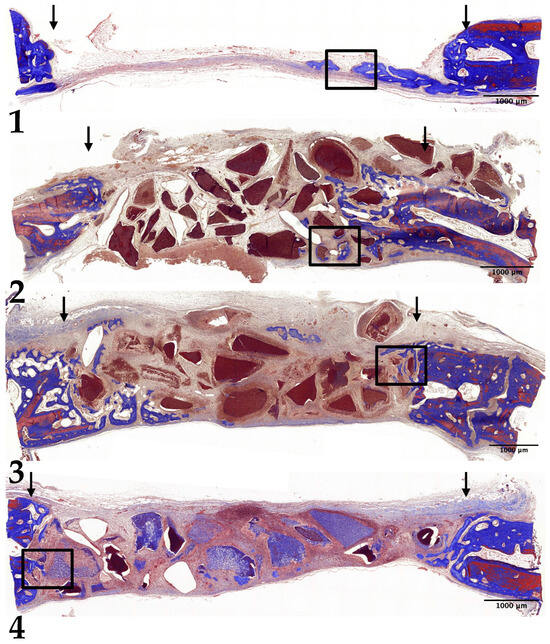

3.3. Four-Week Results

3.4. Eight-Week Results